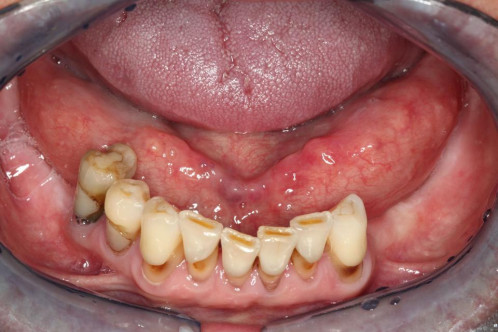

Zu Ihnen in die Praxis kommt eine 54-jährige Patientin und klagt über eine Schwellung unter der rechten Zungeseite. Gelegentlich treten in diesem Bereich Schmerzen auf. Manchmal verspürt sie Ähnliches auch auf der Gegenseite.